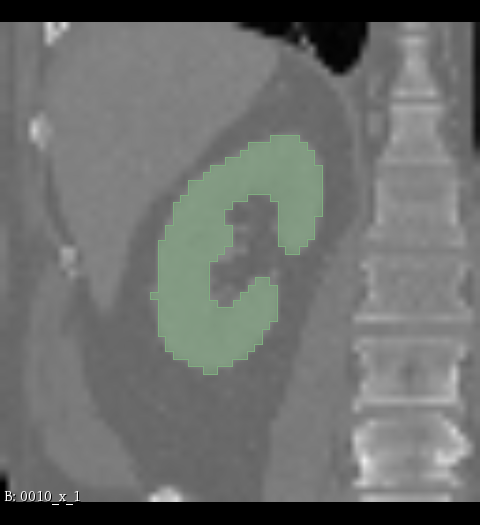

Figure 2: Illustration of the data from the TotalSegmentor data set [32] used in the experiments. The first row shows the axial, coronal and sagittal views passing the center of mass of the kidney in one of the data points. The second row shows the axial, coronal and sagittal views passing the center of mass of the aorta in one of the data points. The third row shows the axial, coronal and sagittal views passing the center of mass of the esophagus in one of the data points.

5.1 Data

The experiments are conducted with respect to the TotalSegmentor data set [32]. This data set contains 1204 CT images with 104 anatomical structures (27 organs, 59 bones, 10 muscles, 8 vessels). To illustrate the effect noise may have on organs with different shape, three different organs are chosen. This includes the right kidney which in general is pretty spherical, the aorta which is tubular and relatively thick and the esophagus which is tubular and relatively thin. For each of the organs, 400 cases is selected and split into 5 folds of 80 cases. Finally, the images are sub-sample to half resolution and patches of 643superscript64364^{3} voxels centered in each of the structures are extracted.